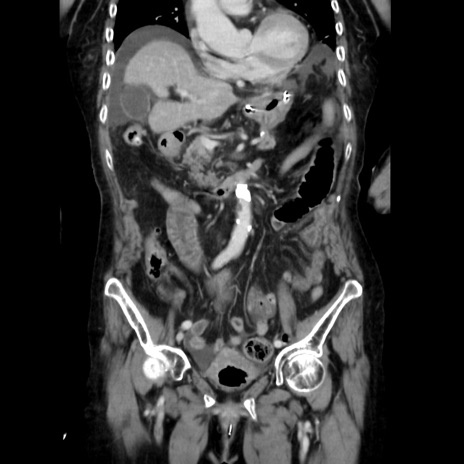

症例40(冠状断像)

【症例】90歳代女性

【主訴】腹痛・嘔吐

【現病歴】 食欲低下、嘔吐があり昨日他院受診。肺炎と診断され入院となる。入院後より腹部全体に圧痛あり。胃管留置され経過みていたが、症状持続するため、

当院転院となる。

【既往歴】胸椎圧迫骨折、胆石症

【身体所見】腹部:中央に激痛あり、圧痛あり、反跳痛不明

【データ】WBC 17100、CRP 18.82

他院CT

冠状断像